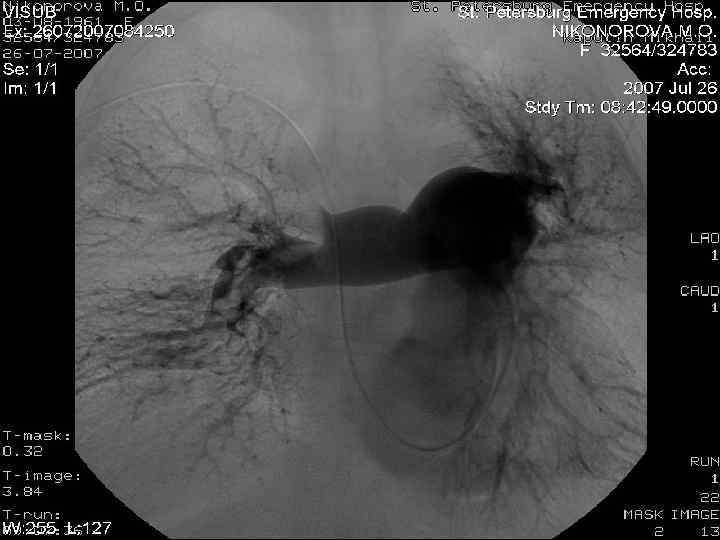

Диагностика ТЭЛА l Клиническая вероятность l Анализ на D-димеры l Результаты СКТ / ангиопульмонографии